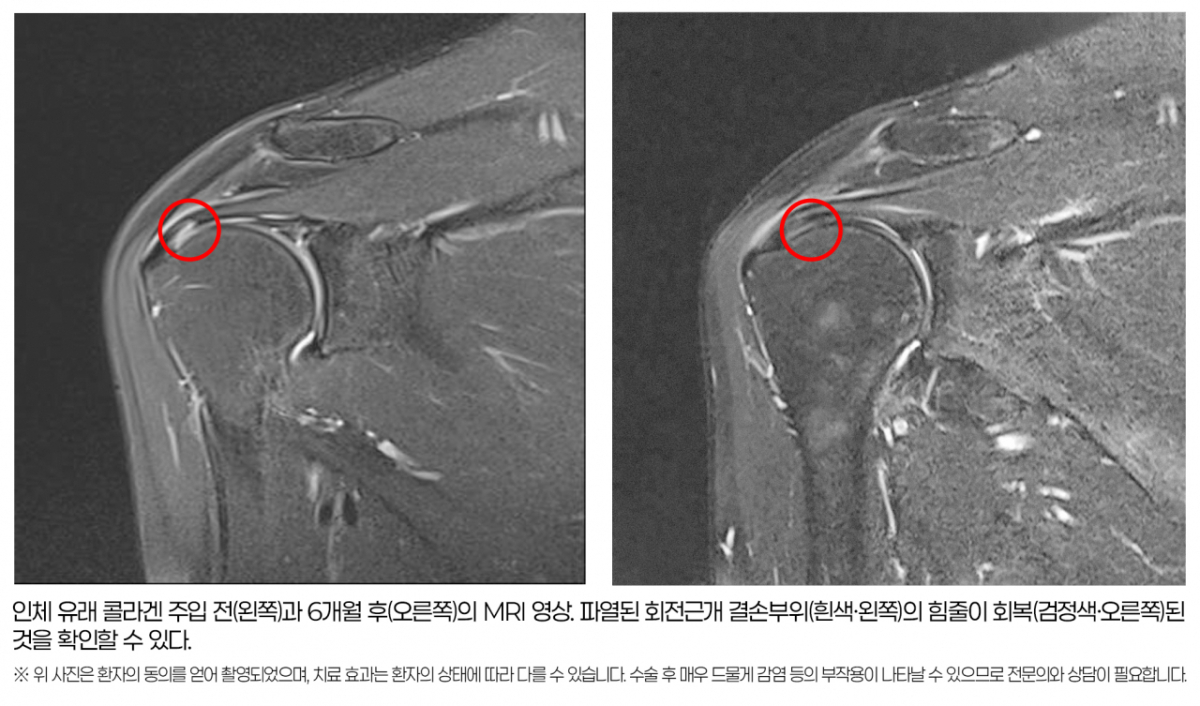

이번 연구의 가장 큰 성과는 MRI를 통해 힘줄의 구조적 회복을 직접 확인했다는 점이다. 6개월 후 MRI 촬영물을 분석했더니 회전근개 손상 지표인 신호강도의 호전 및 파열 부위의 재생이 1㎜ 이상 나타난 환자가 83.33%(30명 중 25명)에 달했다. 파열 부위가 2㎜ 이상 줄어든 환자도 26.66%(30명 중 8명)를 차지했다.

또 심한 염증을 나타내는 체액저류 현상이 환자의 53.55%(30명 중 16명)에서 유의미하게 감소했다. 이는 통계적 유의성(p<0.05)을 확보한 결과로, 콜라겐 주입술이 힘줄의 조직 재생을 돕고 손상으로 인한 염증을 가라앉히며 파열 크기를 줄이는 데 효과 있음을 시사한다.